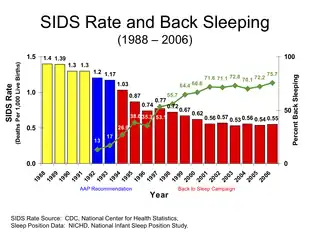

Rates of SIDS vary nearly tenfold in developed countries from one in a thousand to one in ten thousand.[2][11] Globally, it resulted in about 19,200 deaths in 2015, down from 22,000 deaths in 1990.[12][13] SIDS was the third leading cause of death in children less than one year old in the United States in 2011.[14] It is the most common cause of death between one month and one year of age.[7] About 90% of cases happen before six months of age, with it being most frequent between two months and four months of age.[2][7] It is more common in boys than girls.[7] Rates have decreased in areas with "safe sleep campaigns" by up to 80%.[11]

Sleep positioning

Sleeping on the back has been found to reduce the risk of SIDS.[65] It is thus recommended by the American Academy of Pediatrics and promoted as a best practice by the US National Institute of Child Health and Human Development (NICHD) "Safe to Sleep" campaign. The incidence of SIDS has fallen in a number of countries in which this recommendation has been widely adopted.[66] Sleeping on the back does not appear to increase the risk of choking even in those with gastroesophageal reflux disease.[5] While infants in this position may sleep more lightly this is not harmful.[5] Sharing the same room as one's parents but in a different bed may decrease the risk by half.[5]

SIDS was responsible for 0.54 deaths per 1,000 live births in the US in 2005.[33] It is responsible for far fewer deaths than congenital disorders and disorders related to short gestation, though it is the leading cause of death in healthy infants after one month of age.

SIDS deaths in the US decreased from 4,895 in 1992 to 2,247 in 2004.[80] But, during a similar time period, 1989 to 2004, SIDS being listed as the cause of death for sudden infant death (SID) decreased from 80% to 55%.[80] According to John Kattwinkel, chairman of the Centers for Disease Control and Prevention (CDC) Special Task Force on SIDS "A lot of us are concerned that the rate (of SIDS) isn't decreasing significantly, but that a lot of it is just code shifting".[80]